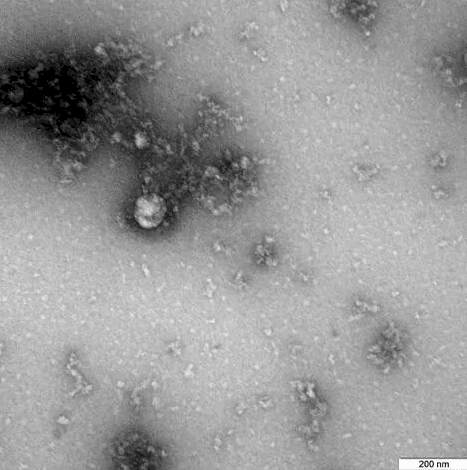

شاهد: أول صورة في العالم للسلالة "البريطانية" من فيروس كورونا

صدى نيوز - تمكن مركز الأبحاث الروسي "فيكتور" من الحصول على أول صورة في العالم للسلالة البريطانية من فيروس كورونا.

جاء ذلك في بيان المركز الإعلامي للوكالة الفدرالية لحماية حقوق المستهلك "روس تريب نادزور"، حيث ذكر البيان أنها المرة الأولى في العالم التي يتم فيها تصوير السلالة البريطانية لفيروس كورونا من مريض في ديسمبر 2020. بعد الحصول على صورة الفيروس تحت المجهر كجزء من دراسة خصائصه.

وقد تمكن نظام اختبارات تفاعل البوليميراز المتسلسل التي طورها مركز "فيكتور" التابع لـ "روس تريب نادزور" من اكتشاف العدوى بالسلالة "البريطانية"، حيث يستطيع النظام تمييز الفرق بين الفيروس المتغير والأشكال غير المتحولة، وتمكن المجهر الإلكتروني الروسي الذي بلغت نسبة تكبيره 100 ألف مرة من تصوير الطفرة "البريطانية" للفيروس.